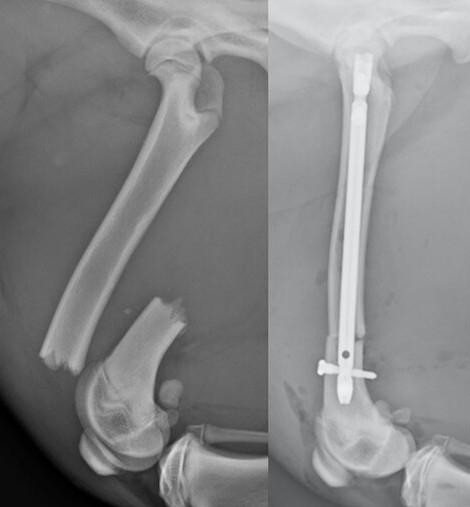

Interlocking Nail

Interlocking nails involve placement of a large metal rod within the bone which is then secured with multiple small bolts. Interlocking nails are particularly strong because they are placed within the center of the bone where they can resist forces most effectively. However, only certain bones can receive an interlocking nail. We also disrupt the normal curvature of the bone which can overstress the implant or affect limb alignment.